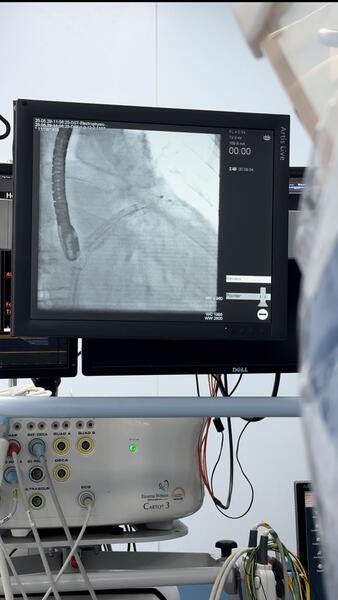

В Научно-исследовательском институте кардиологии и внутренних болезней успешно проведена высокотехнологичная операция по имплантации окклюдера ушка левого предсердия. Сегодня НИИКВБ является единственным медицинским центром в Казахстане, где выполняются такие вмешательства.

По его словам, учитывая жалобы и данные анамнеза, а также высокие ишемические и геморрагические риски, пациентке было рекомендовано проведение рентгенэндоваскулярной окклюзии ушка левого предсердия.

Операция прошла успешно, и уже на шестые сутки пациентку выписали из клиники. Для контроля состояния через три месяца ей предстоит пройти чрезпищеводную эхокардиографию.